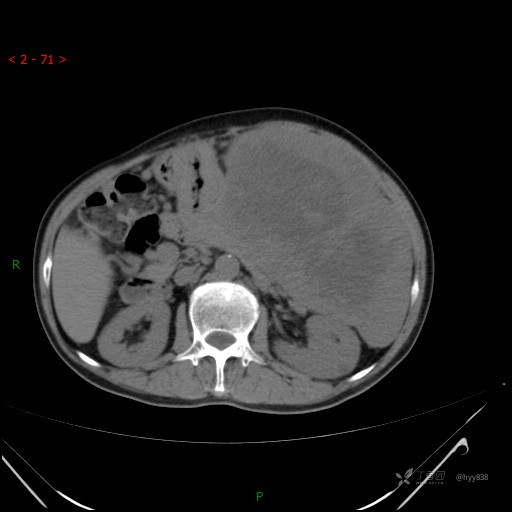

增强静脉期